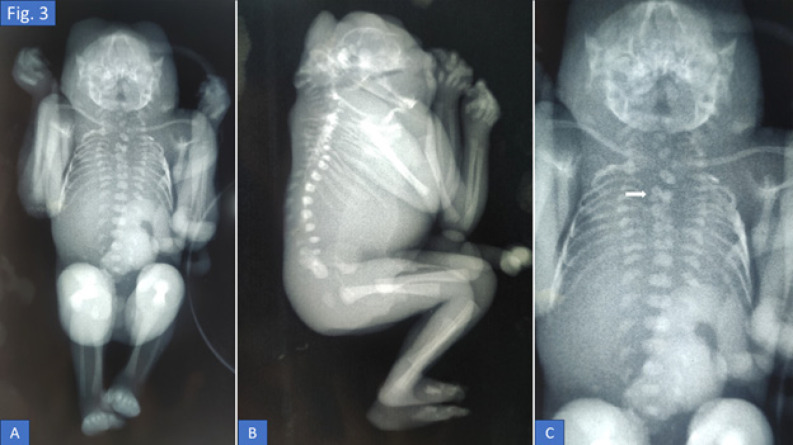

Neural tube defects (NTDs) are severe congenital anomalies resulting from improper neural tube closure. Craniorachischisis totalis, the most extreme form, involves failure of neural tube formation along the entire cranio-spinal axis. This rare condition is fatal, with limited reported cases globally. We report a case of a 35-year-old G3P1L1A1 woman admitted at 20 weeks and 4 days gestation for medical termination of pregnancy following second-trimester ultrasound findings of anencephaly and spinal dysraphism. The patient began folic acid supplementation only after pregnancy confirmation. The fetus exhibited acrania, bifid vertebrae, exposed neural tissue, frog-eye deformity, and limb contractures. Butterfly vertebrae was observed in infantogram. Retrospective ultrasound review revealed an absent cranial vault, disorganized brain matter, and a large open spinal defect extending to the upper lumbar region. Genetic and infectious panels were largely unremarkable, except for reactive rubella IgG. Craniorachischisis totalis arises from failure of neural tube closure, potentially linked to genetic mutations, folate deficiency, and multiple maternal risk factors. Here, we also revisit the various theories of neural tube closure. Early prenatal diagnosis and counseling are critical for managing craniorachischisis. Periconceptional folic acid supplementation remains the most effective preventive measure.